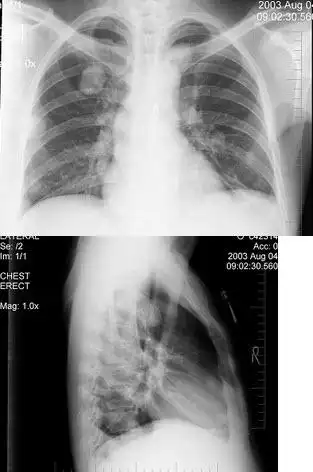

胸片提示病变加重,左肺大部分实变,右肺中上野斑片阴影(图2),为进一步

疑难问题,看看这张胸片

淋巴管炎和肿大的肺门或纵膈淋巴结组成的哑铃状阴影

分布平均,密度相似,巨细一致的粟粒状结节(原发性肺结核,哑铃状的原发